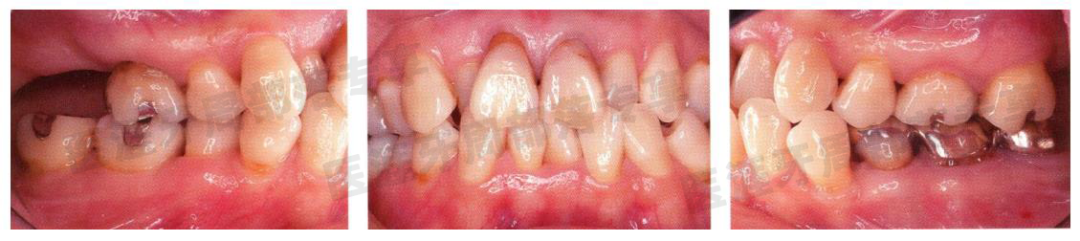

初诊时33 岁的女性患者

怎么选洁牙器械5个要点带你学习器械洁牙_https://www.jmylbn.com_新闻资讯_第36张

初诊时口内照(1997 年11 月) 虽有菌斑附着,但刷牙情况并不特别差